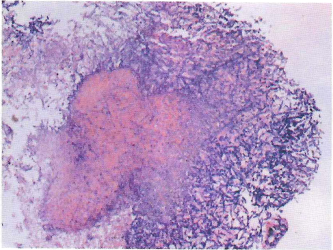

入院第5天,化验回报血GM试验11.05 pg/ml,BALF GM试验10.70 pg/ml。BALF培养:黄曲霉、烟曲霉。血培养为泛耐药鲍曼不动杆菌。气管镜下组织活检提示大量真菌孢子及菌丝(图3)。患者氧合仍难以维持,继而出现循环进一步衰竭。第5天夜间患者死亡。

图3  气管镜下组织活检提示大量真菌孢子及菌丝